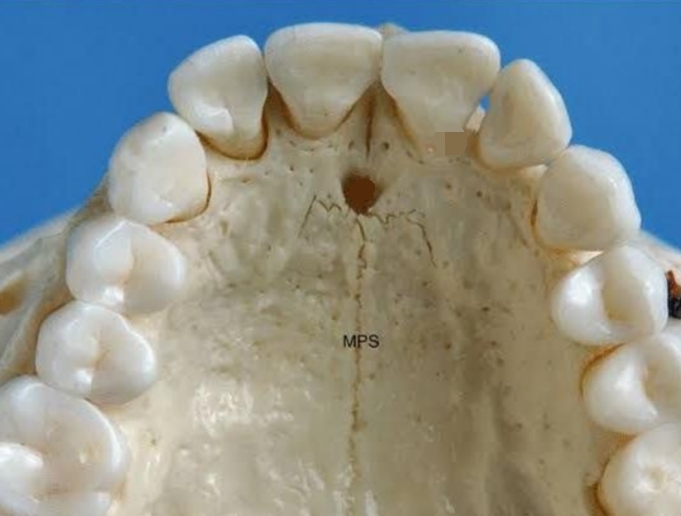

Located in anterior portion of hard palate

Location for anesthesia for anterior teeth

Incisive Canal and Foramen